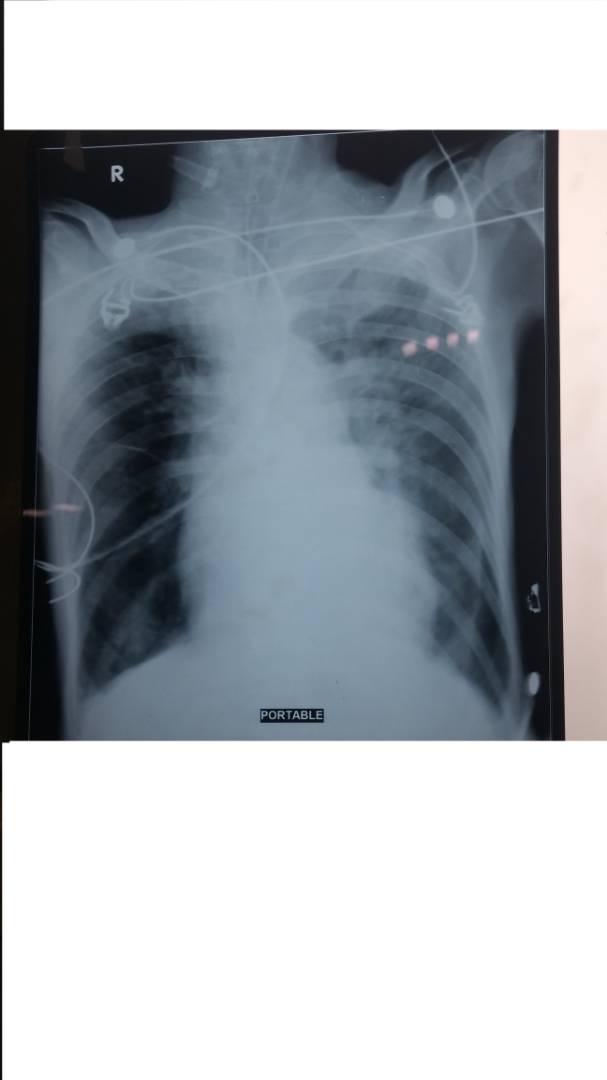

2nd one

The most recent one